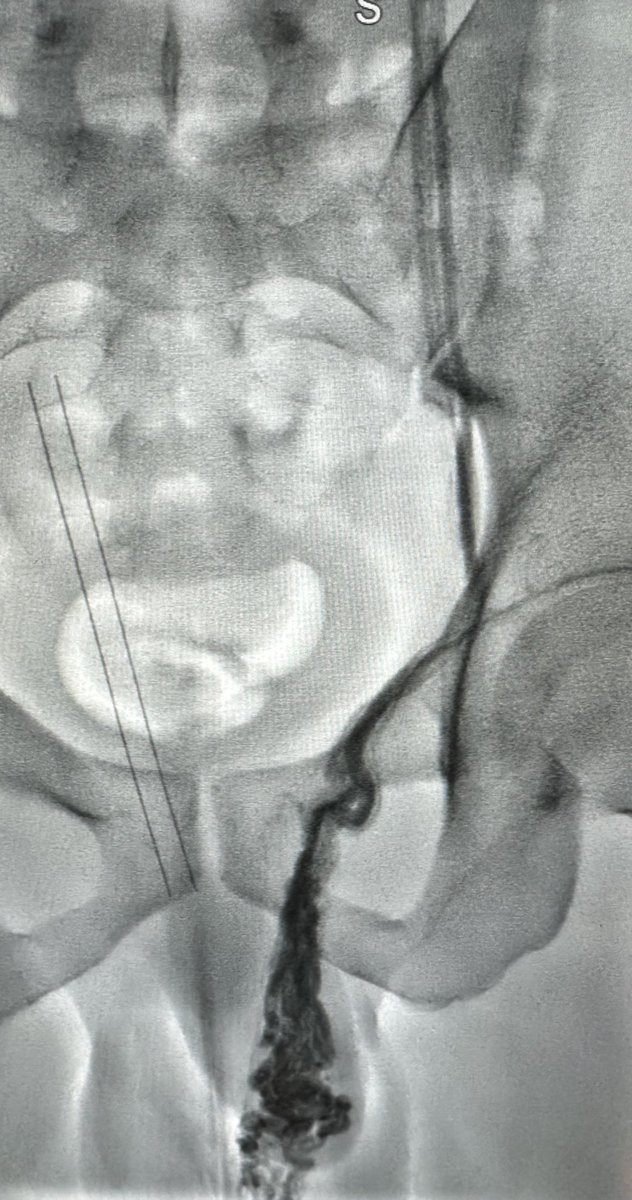

في رحاب منى، جمعتني هذه الصورة بأخي الذي ولدته لي الأيام HaniBadahdah, MD تعاهدنا أن نكون صوتاً و احداً في التوعية، وعملاً مستمراً لمحاربة #البتر رسالتنا الوقاية أولاً، والعلاج مبكراً ، والبتر ليس حتمياً #القدم_السكرية #وعي_وحياة #حج_1446 #حج_بصحة